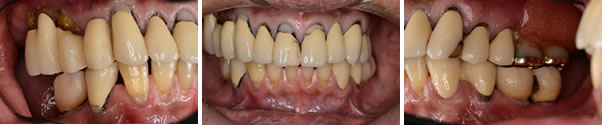

この患者さんは、以前から何回も奥歯が腫れたり、前歯の被せものが取れたりしていました。今回はお口全体をしっかり治療したいとうことで来院しました。

問題点は咬み合わせが崩壊しているため、咬合再構成しないといけないことと、以前にインプラント治療がされているので、咬合再構成するときお口にはいっているインプラントをどのように対応するかです。

治療中

現在プロビジョナルレストレション(治療用の仮歯)で咬み合わせを変え経過をみています。上顎奥歯のインプラント治療には骨が不足しているためサイナスリフトを併用しています。この仮歯をベースにして、最終的な被せものを製作していきます。